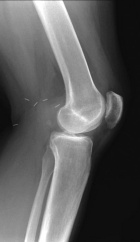

T.F. - 34 year old woman with a history of arthroscopic and open left knee surgeries in 2003 presenting with increased left knee pain and swelling

Zoom image: Radiological image Radiological image.

Zoom image: Cell stain Cell stain.